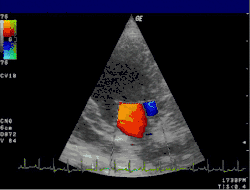

![]() |

| 1 : Atrium gauche – 2 : Jet de régurgitation

LV : Ventricule gauche – RV : Ventricule droit – RA : Atrium droit | |

L'échocardiographie reste l'examen clé[15]. Il permet de quantifier la fuite et d'évaluer son retentissement sur les différentes cavités : dilatation de l'atrium gauche et/ou du ventricule gauche, altération de la fonction systolique avec diminution de la fraction d'éjection. En outre, l'échocardiographie permet le plus souvent d'étayer les hypothèses sur le mécanisme de l’insuffisance (dilatation de l’anneau, fermeture incomplète de la valve, endocardite, prolapsus, retournement du bord du feuillet (flail leaflet), et la localisation des éventuelles anomalies; pouvant orienter le type de traitement. Si besoin, l'examen peut être complété d'une échographie transœsophagienne permettant de mieux visualiser les différentes structures composant la valve.

L'échocardiographie Doppler est toujours associé à l'échocardiographie et permet de visualiser les vitesses du sang sous forme de codage en couleurs. Il permet ainsi de visualiser le jet de l'insuffisance mitrale dans l'atrium gauche. Les dimensions de ce jet permettent déjà une estimation grossière du degré de sévérité de l'insuffisance.